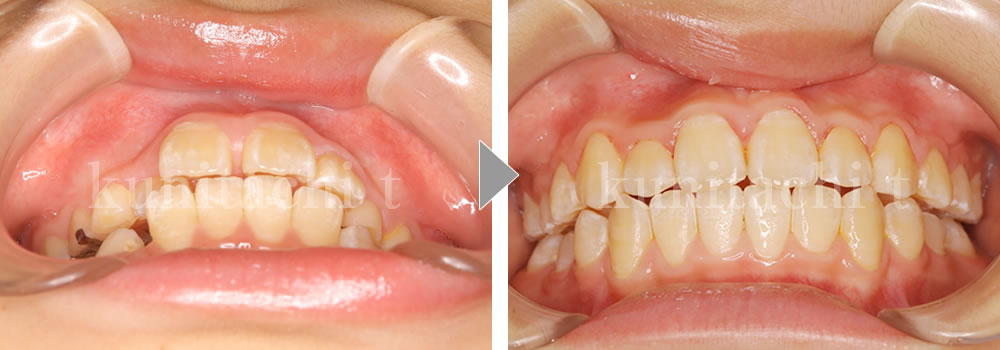

小児矯正治療前後の比較

これから小臼歯が生えそろい、しっかり噛めるようになっていきます。でも、低位舌があると歯並びに影響が出ることも…。「上顎に舌!唇をとじる!鼻呼吸!」良い歯並びをつくるおまじないです。

第2大臼歯も萌出して永久歯列が良い状態で完成しました。